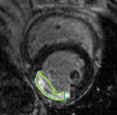

4.2 Visual assessment

We select the case that achieves the highest and lowest dice score for visual assessment. Fig. 4 shows example segmentation results where the proposed method achieved the highest agreement with the ground truth delineations. Fig. 5 shows example segmentation results where the proposed method achieved the lowest agreement with the ground truth delineations.